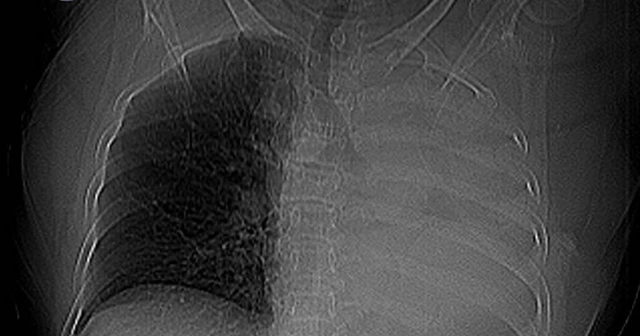

Bệnh nhân là bà T.B. (78 tuổi, trú Đà Nẵng ). Sau khi chụp X-quang ngực, các bác sĩ phát hiện hình ảnh mờ đậm đều toàn bộ trường phổi trái. Kết quả CT cho thấy cụ bà bị xẹp toàn bộ phổi trái do khối tổn thương nằm trong lòng phế quản gốc trái, nghi ngờ u phế quản hoặc dị vật đường thở.

Sặc một viên thuốc, cụ bà xẹp toàn bộ phổi trái- Ảnh 1.

Phim X-quang ngực cho thấy mờ toàn bộ phổi trái.